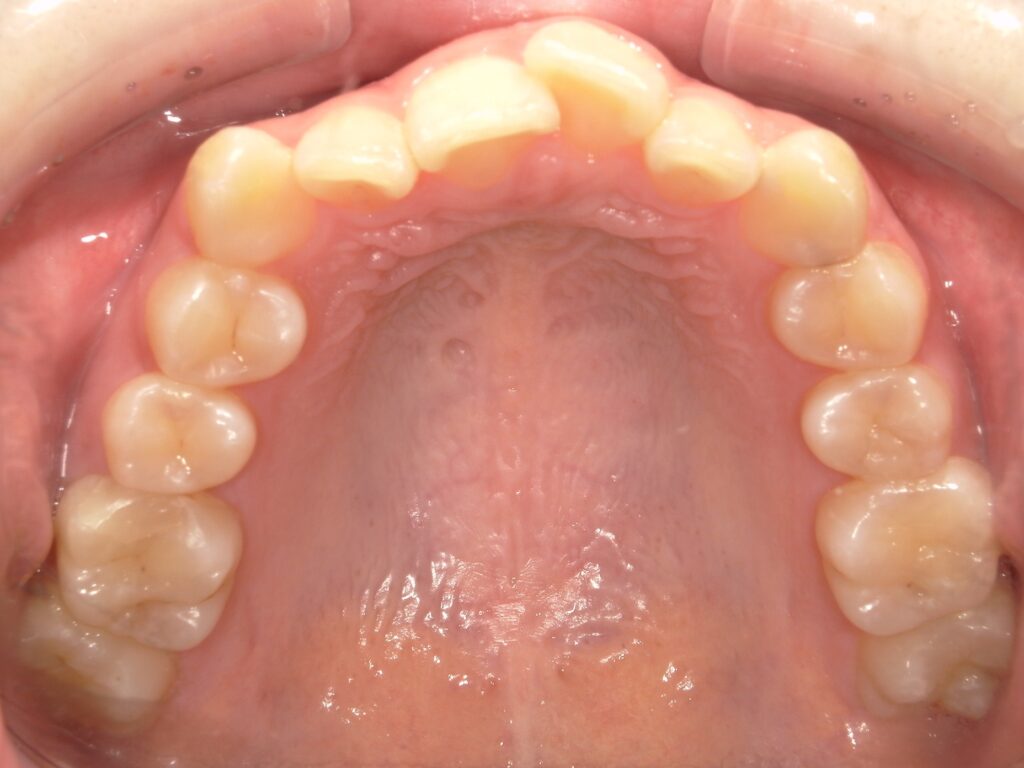

Before

After

ガタつき

- 40代女性

- 主訴:ガタつき

- 矯正方法:インビザラインの抜歯矯正

- 治療期間:11ヶ月

- 治療費:935,000円

- その他ご要望:差し歯があるが矯正できるか、かぶせ物が多いので矯正に影響ないか、金属アレルギーあり。

- 詳しくはこちら

ご相談内容 ガタつきが気になると40代女性からのご相談 現状と治療方針 ガタつきが見られます。特に下の前歯の右側の2番目の歯は完全に並ぶスペースがありません。そのため、下の歯を1本抜歯して治療を行いました。 治療結果 ガタつきを11ヶ月で改善することができました。 振り返り 今回の患者様はガタつきが強く、顎のスペースに対して歯が並ぶスペースが不足していたため、片側の抜歯矯正を行いました。上の前歯2本が差し歯のため、歯が動くのか心配されていましたが問題なく動いています。また、かぶせ物が多いことも矯正に影響がないか気にされていましたが、こちらも問題なく治療は順調に進みました。金属アレルギーでしたがマウスピースのため問題なく矯正することができました。 リスク・副作用 マウスピースの装着時間を守っていただけないと矯正治療に時間がかかり、場合によっては治療がうまく進まない可能性があります。